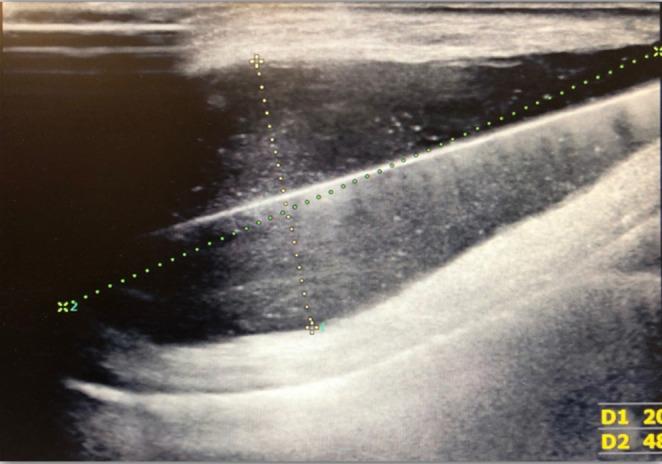

Abscess after cardiac pacemaker implantation: A case report.

This is a report of one of the most serious complications of the cardiac pacemaker implantation - infection of the implanted system. We present the case, which was misdiagnosed at the beginning and after cardiological consultation it was decided to immediately remove the peacemaker and transfer the patient to the Cardiological Department.

这是一篇关于心脏起搏器植入最严重并发症之一——植入系统感染的报告。我们呈现该病例,其起初被误诊,经心内科会诊后决定立即移除起搏器并将患者转至心内科。